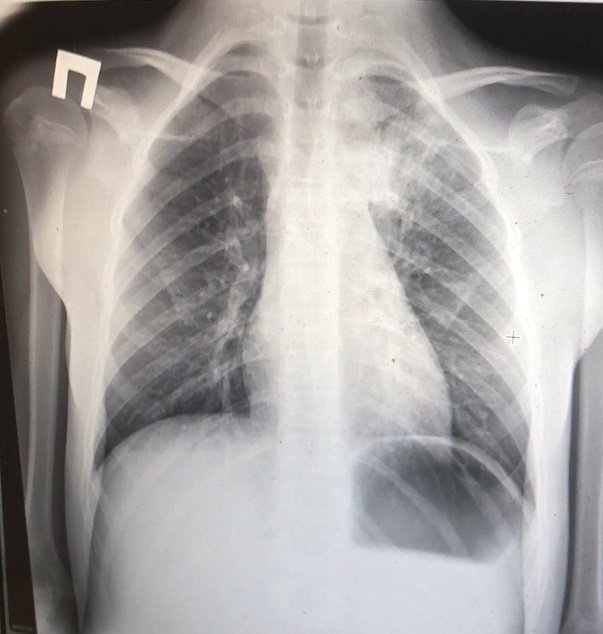

Рентгенография грудной клетки – один из наиболее информативных методов диагностики заболеваний дыхательной системы, включая пневмонию. Он позволяет не только выявить патологический процесс, определить его локализацию и особенности, но и оценить эффективность проводимого лечения. Как же выглядят рентгенологические признаки пневмонии на снимках, и как проводится рентгенография при данной патологии?

После проведения рентгенографии снимки должен изучить специалист, и на основе полученных данных и результатов других исследований сделать соответствующие выводы и поставить диагноз. В норме легкие и бронхи человека выглядят следующим образом:

• легочные доли имеют одинаковый, равномерный черный оттенок;

• в районе сердца наблюдается белый просвет;

• ребра и ключицы серые, с привычными очертаниями;

• купола диафрагмы белого цвета;

• позвоночный столб расположен в центре.

Признаки пневмонии на рентгеновском снимке во многом зависят от формы заболевания и его стадии, а также от локализации патологического процесса. Если исследование показало признаки пневмонии, необходимо как можно скорее приступить к лечению – запущенный патологический процесс опасен не только для здоровья, но и для жизни человека.

Первый признак пневмонии на рентгеновском снимке – появление очагов затемнения с неровными контурами в разных частях легкого, которые могут иметь разный размер, от 3-4-х до 12 мм.

Тени различают по внешнему виду (круглые, овальные кольцевидные) и интенсивности окраски – чем темнее пятно, тем сильнее выражен патологический процесс.